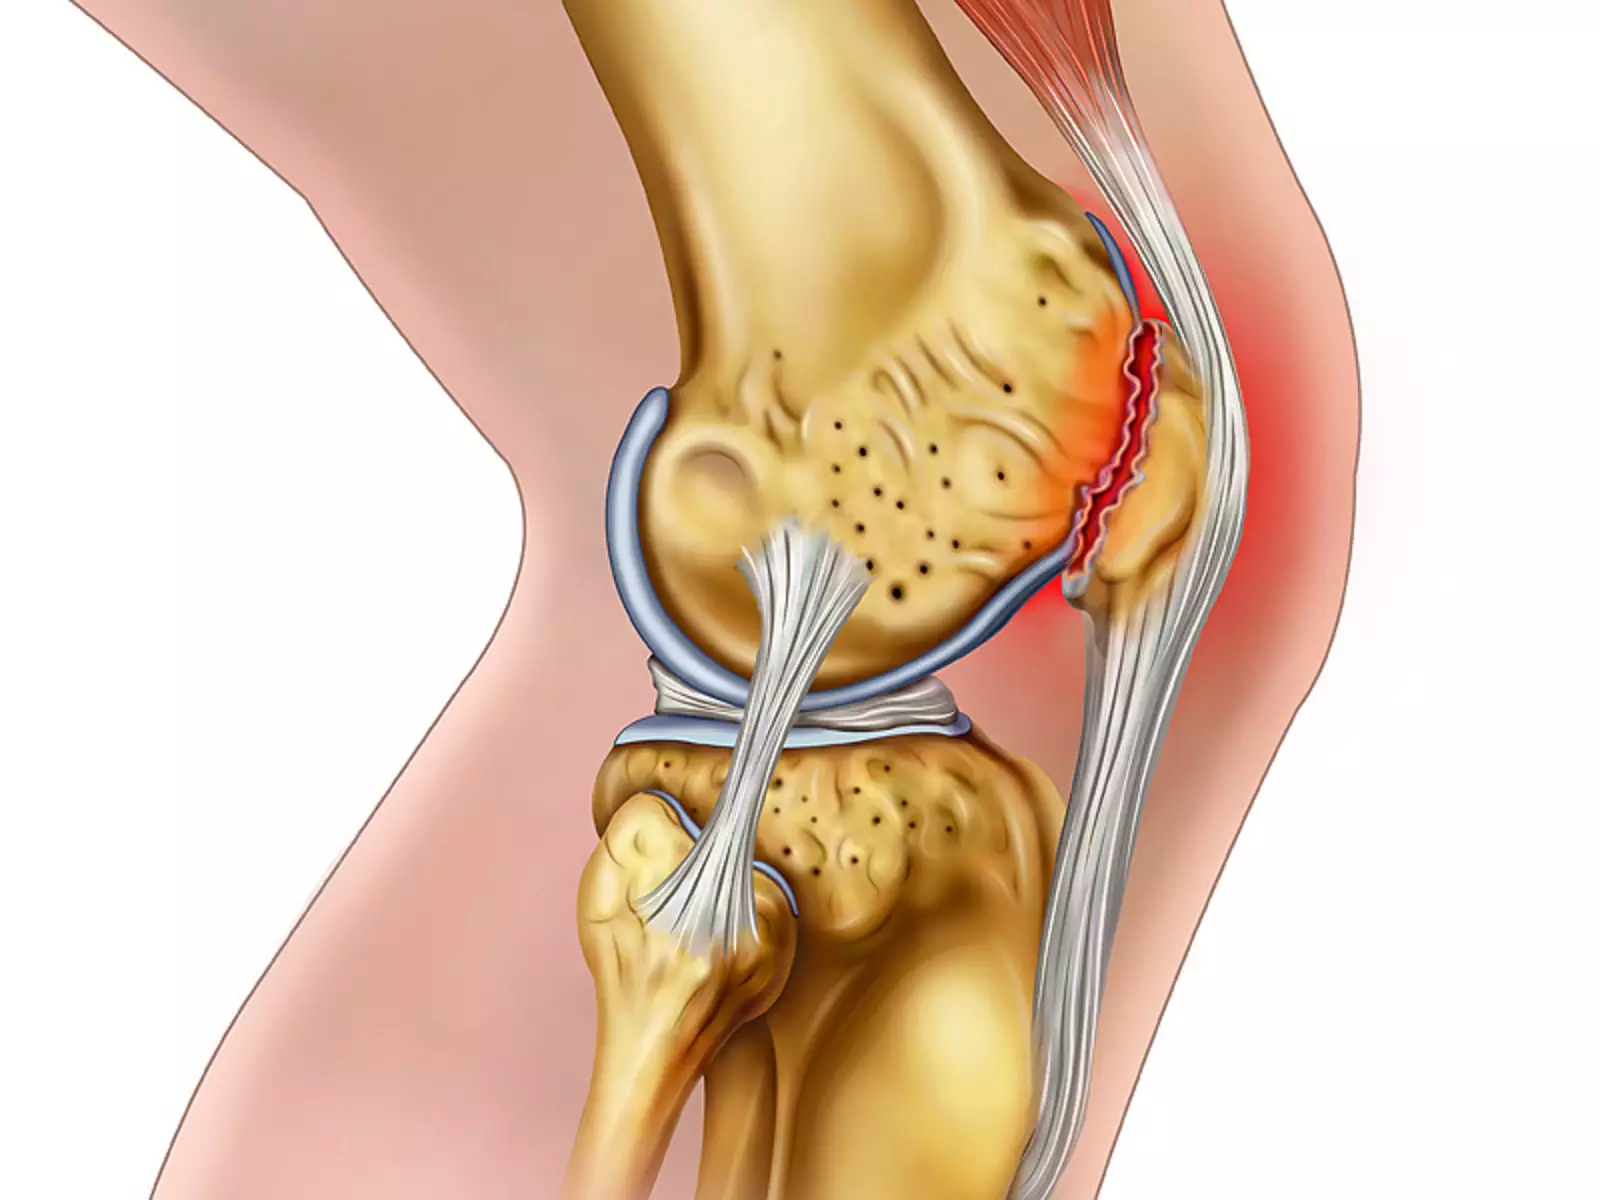

Анатомические изображения менисков и коленного сустава

Раздел: Иллюстрированные советы